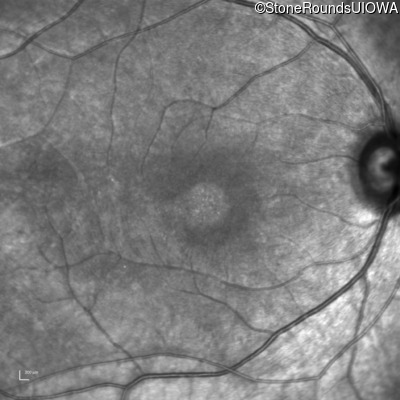

Infrared Fundus Photograph - Left - 20/200 +2

Exemplar